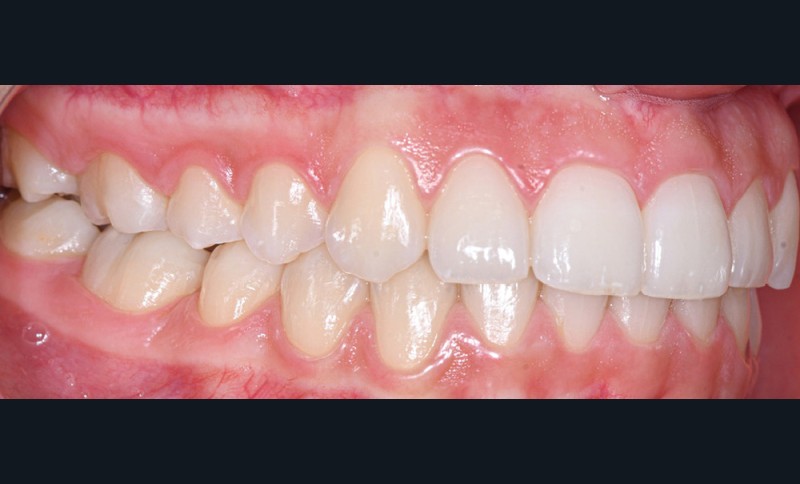

Nous détaillons la technique à travers le cas d’une jeune fille de 18 ans présentant des lésions carieuses sur quatre dents (fig. 1 à 14).